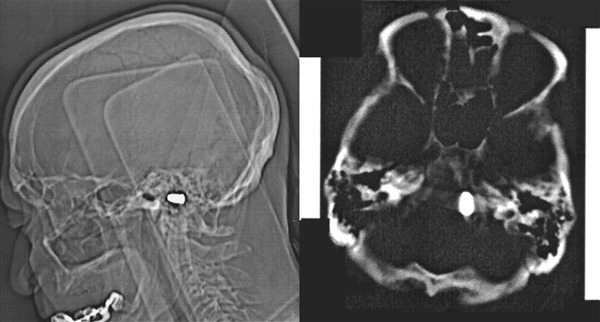

Каково было их удивление, найти прямо у основания черепа рядом с “foramen magnum” (радиологи меня поправят) настоящую пулю.

Courtesy of Maya Safarova, M.D. and Marat Ezhov, M.D., Ph.D.

Оказывается, когда пациенту было три года, в него случайно выстрелил его брат. Причем ни куда-нибудь, а прямо в голову. Пуля вошла в область ноздри и уже никогда не выходила.

Ровно 82 года назад, хирурги отказались оперировать ребенка сославшись на возможные не обратимые осложнения.

Как мы видим сегодня, человек прожил с пулей в голове 82 года. Он сделал успешную карьеру инженера и дожил до преклонных лет.

Случай уникальный, пуля не задела и в последствии не сдавила, ни один из жизненно-важных центров.

Решение врачей сегодняшних дней, повторяет заключение 82-х летней давности: “пулю не вынимать”, с единственной оговоркой: МРТ противопоказан.